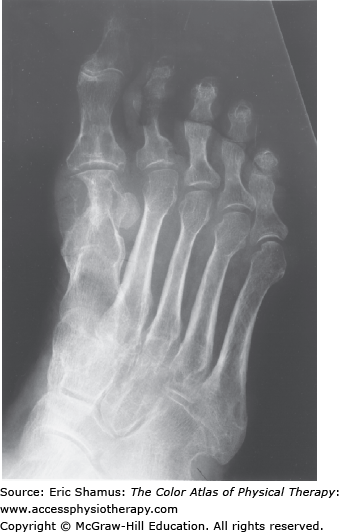

Sesamoiditis

Scenario: Patient is a 56-year-old plumber. Two weeks ago he was working in a tight area under the sink and had his ankle dorsiflexed with all of the weight on his forefoot. The toes were all into extension. When he stood up he had pain under his big toe from what he described as an over stretching. He tried to put some ice on his foot. He presents with decreased motion at the first metatarsophalangeal (MTP) joint with swelling. He is having difficulty pushing off on the foot when trying to go up the ladder. Upon palpation he is point tenderness at the flexor hallicus longus and both sesamoids.

Answer with rationale: A. Decreased push off because of the discomfort of pressure under the big toe. Increased supination and external rotation of the foot, forefoot abduction and lateral whip. These alterations come from the attempt to release pressure on the great toe and normalize the gait pattern.